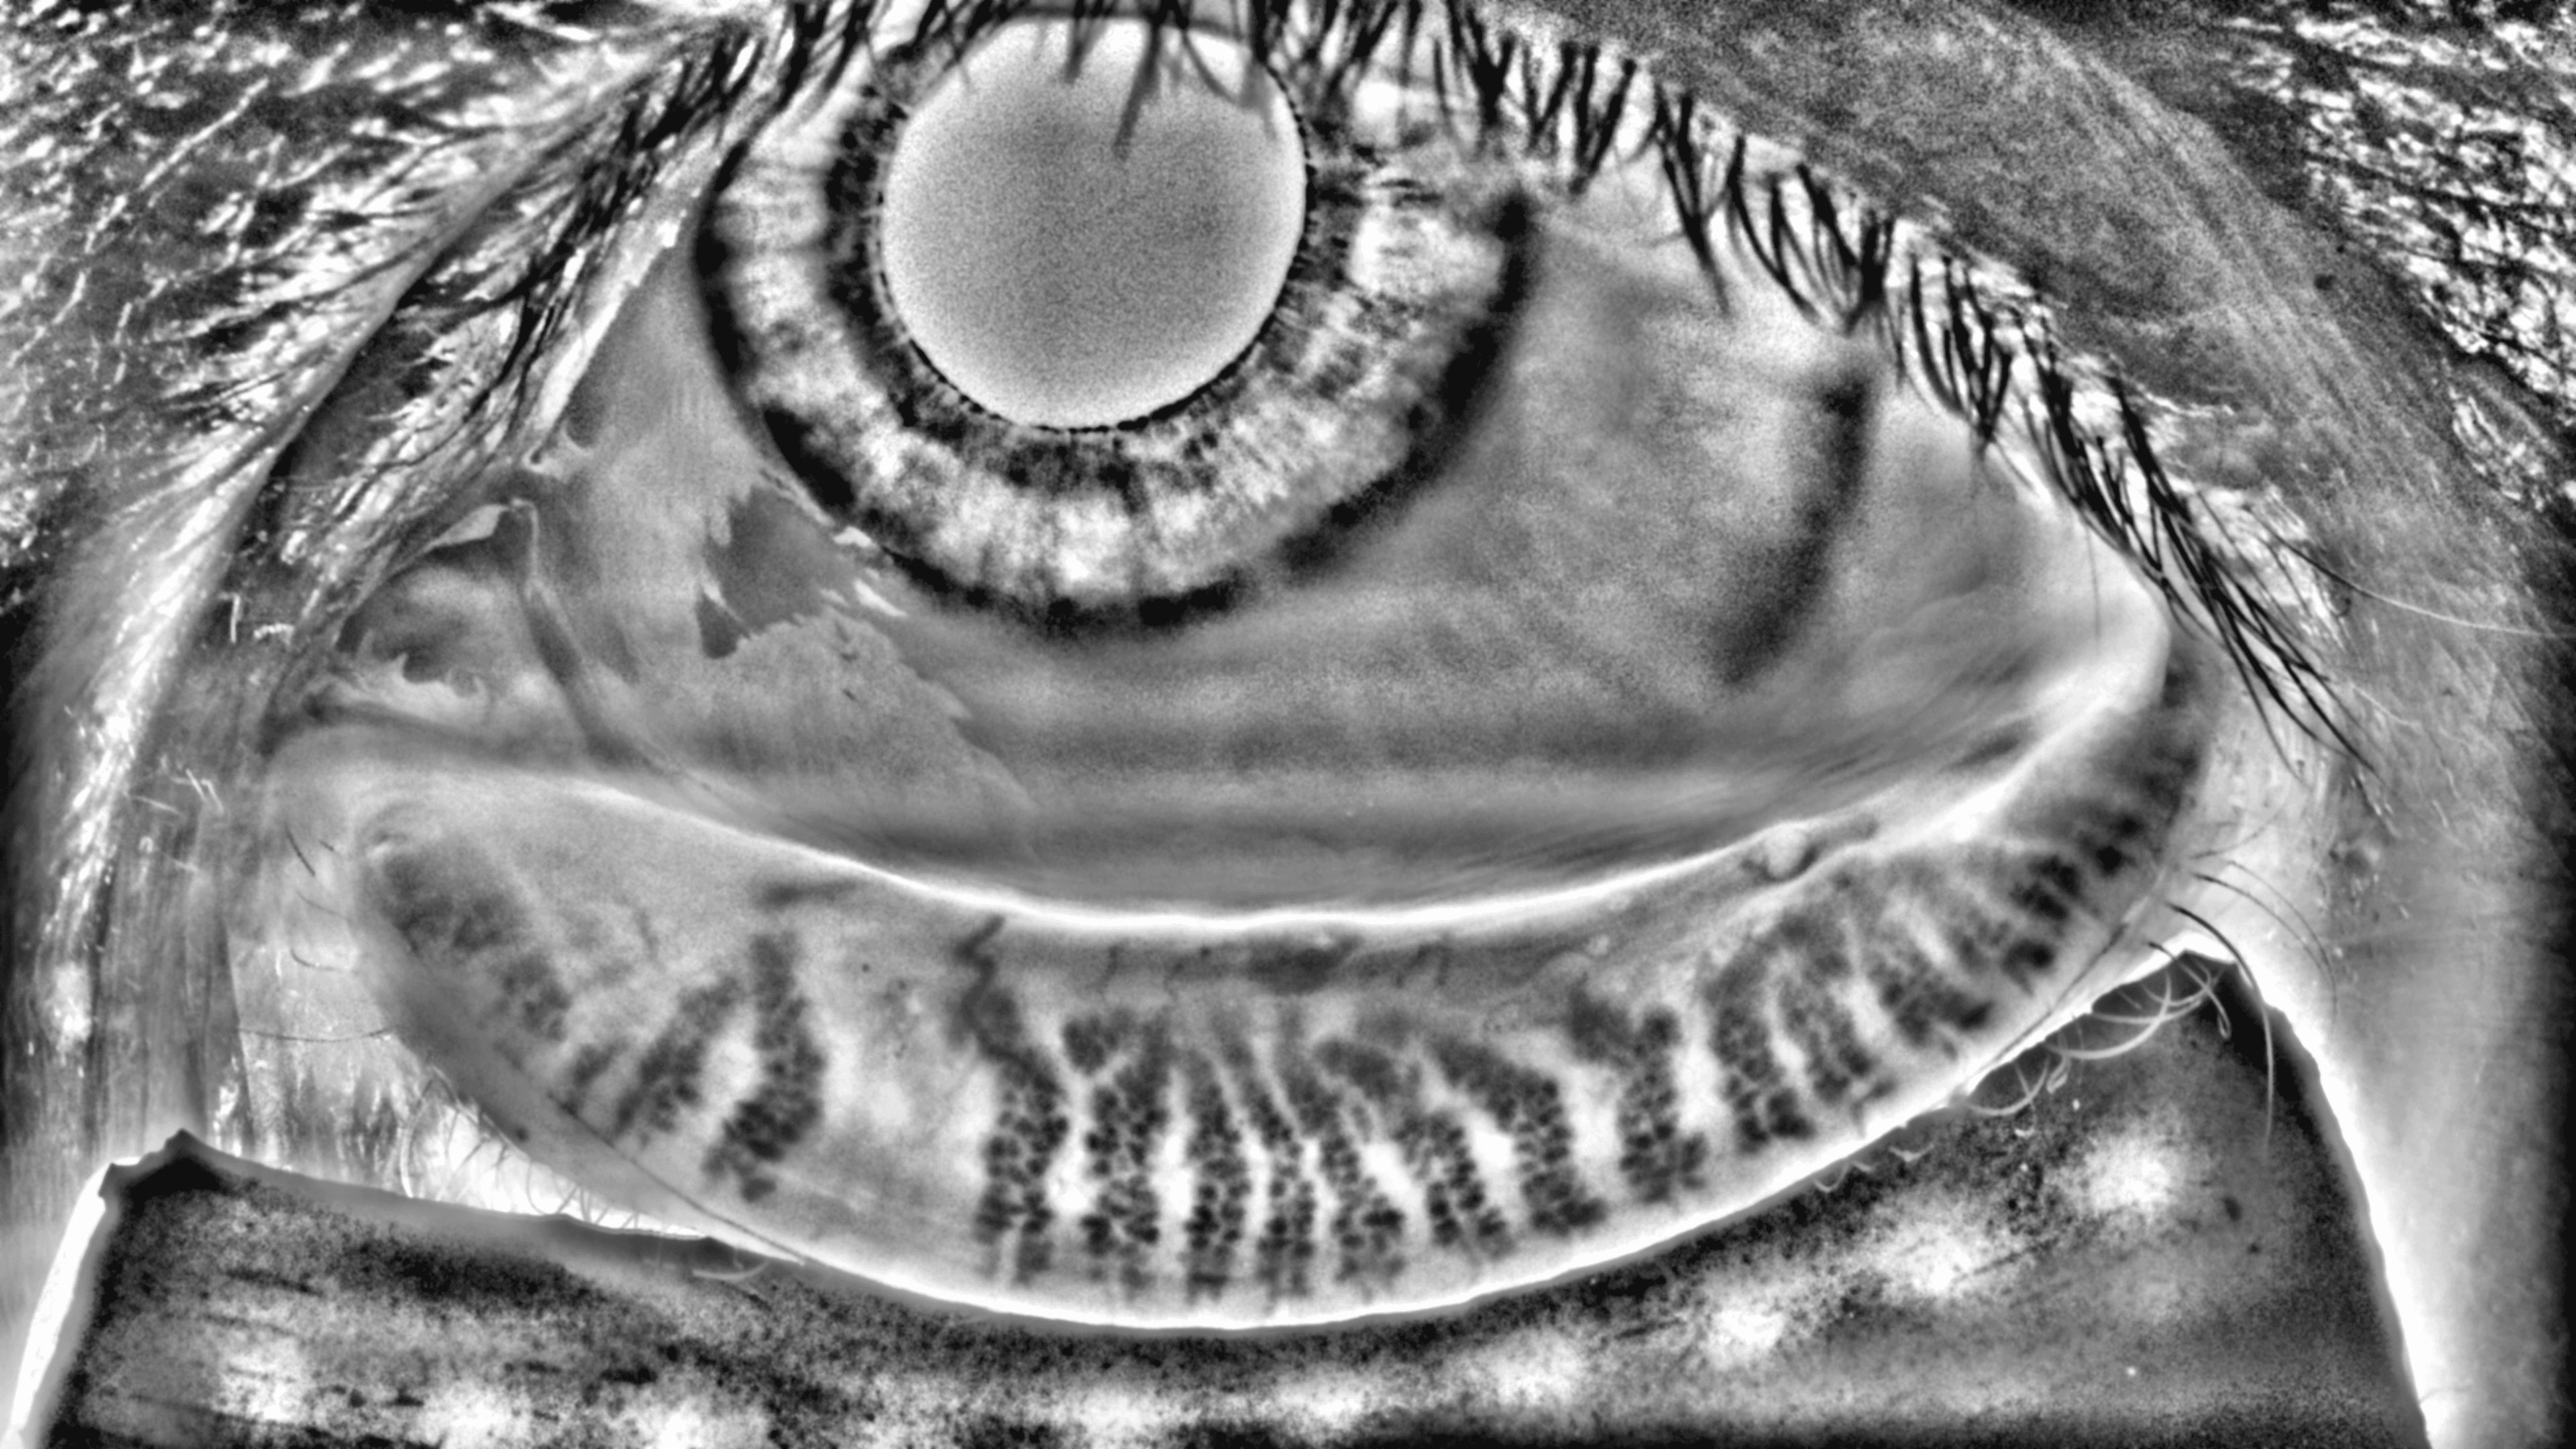

Capture and visualize meibomian gland structure, blink dynamics, tear film appearance, fluorescein imaging, and patient-reported symptoms using a single, compact device designed to integrate seamlessly into existing clinical setups.

AI-Enhanced Visualization

See More with AI-Assisted

Real-Time Visualization

AI-assisted image processing enhances the visibility of ocular surface features, reducing time required manual image adjustments and allowing clinicians to focus on efficient clinical review. Operating directly on the live video stream, it provides immediate visual feedback that supports faster alignment, more confident image capture, and a smoother workflow.